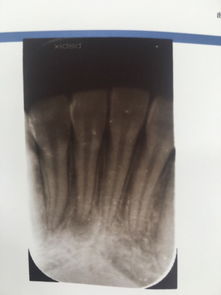

牙根發(fā)炎的原因有哪些?

導致牙根發(fā)炎的因素有很多,出現(xiàn)的時候要及時進行治療。那么,牙根發(fā)炎怎么辦?

牙根炎癥的存在,會反復腫痛,影響牙齒的咀嚼功能,嚴重會造成牙的喪失。這樣不僅會影響消化功能,而且在童年時期會影響面部的發(fā)育。此外,有的牙根炎癥進一步發(fā)展會導致全身其它器官的病變。